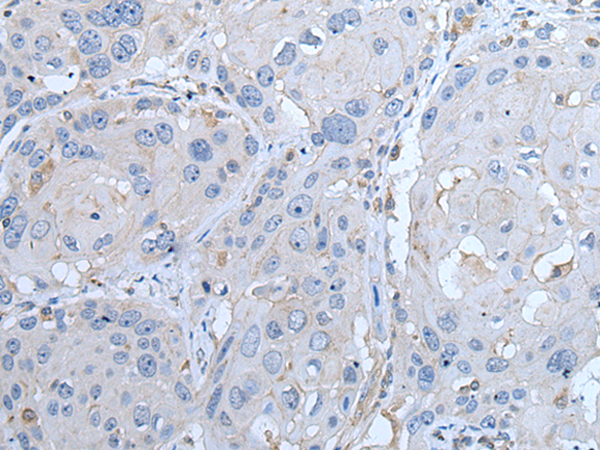

ELISA, IHC |

IHC positive control: |

Human esophagus cancer and human breast cancer |

IHC Recommend dilution: |

25-100 |